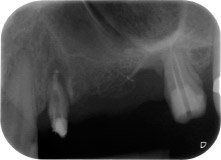

Una paziente donna di 58 anni lamentava dolore e aumentata mobilità del dente di appoggio del ponte 24. Era presente infiammazione periodontale con tasche di profondità di 7 mm a livello mesiobuccale e di più di 12 mm a livello distale, nonché coinvolgimento di terzo grado della forcazione. Inoltre, la radiografia rivelava una lesione periodontale estensiva attorno alla regione apicale del dente pretrattato 24 (in altro luogo) a livello endodontico (Fig. 1).

Tutto il tessuto osseo vestibolare e distale era mancante in corrispondenza della radice buccale. La possibilità di attacco era essenzialmente ristretta alla radice palatale, evidenziando la prognosi negativa preliminare. Anche il dente 27 mostrava un punto di attacco orizzontale ridotto e una rarefazione apicale minima (cfr. Fig. 1), senza sintomi clinici.